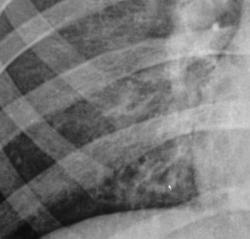

После цифровой обработки изображения и увеличения его (иллюстрации 2, 3, 4) медио – базально определяются округлой, каплевидной и неправильной формы просветления, по всей видимости бронхоэктазы дизонтогенетического генеза.

Вокруг бронхоэктазов определяется снижение прозрачности легочной ткани.